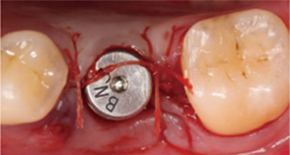

1. Exposing bone after incision

2. Large implant hole after multiple drilling

3. Placing implant